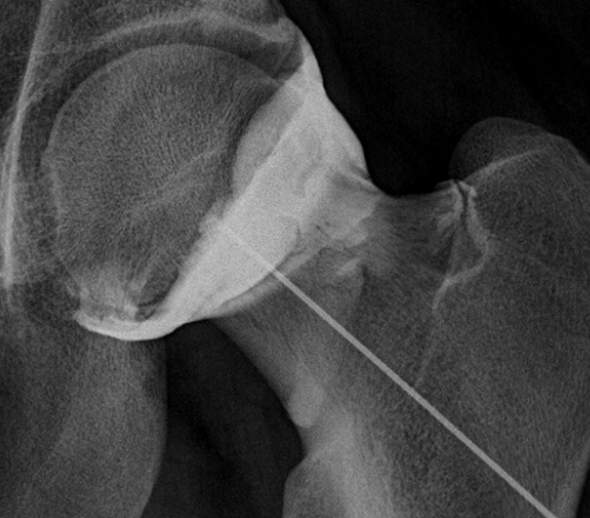

Radiographie et Arthro-IRM

La radiographie, l'arthro-IRM et/ou l'arthroscanner permettront de faire le diagnoctic

Infiltration

L'infiltration de hanche, les antalgiques et anti-inflammatoire, la kinésithérapie sera la traitement initial